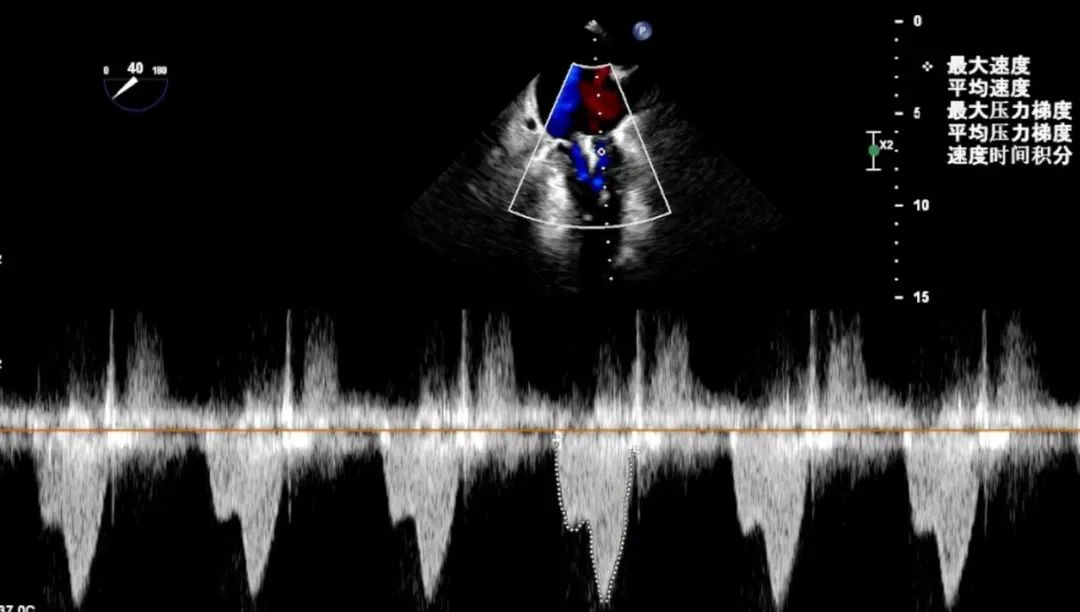

跨瓣压差

关闭瓣膜夹,超声评估,由于病变位置较宽,彩色多普勒可见外侧残余反流,二尖瓣跨瓣压差2mmHg,决定外侧再置入一枚瓣膜夹。